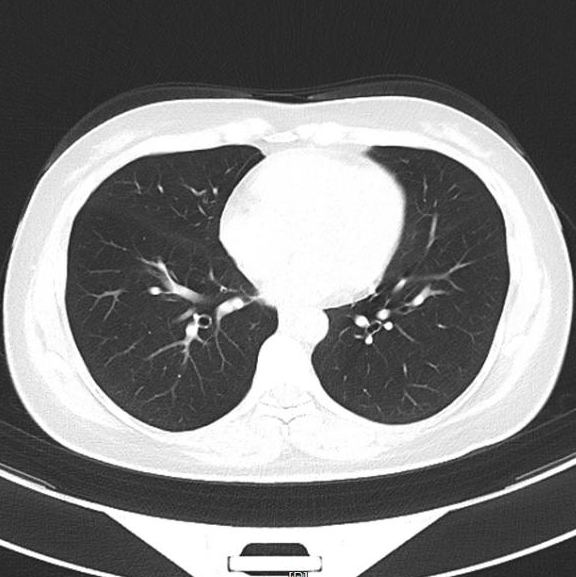

▲治疗后1月

▲治疗后2年半

▲治疗前